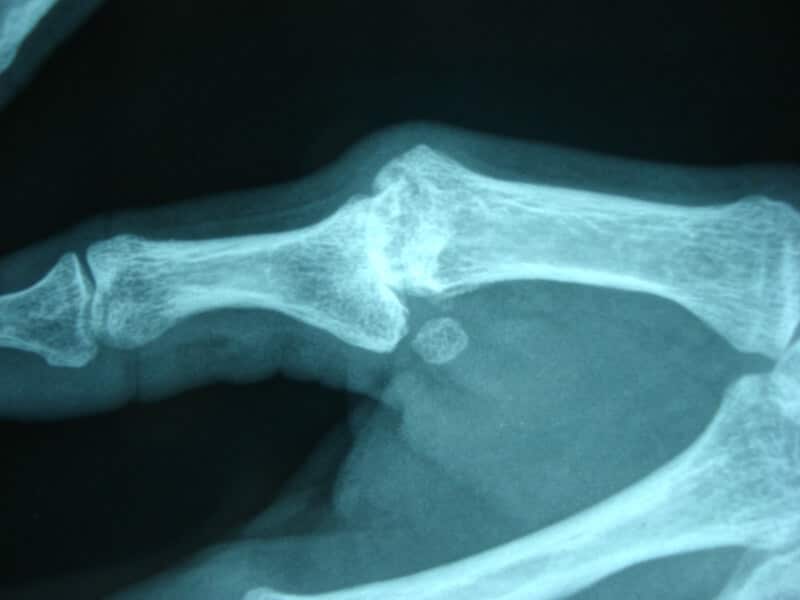

consultation pour entorse pouce paris

Fracture à dépister de la zone d'insertion du ligament externe sur P1